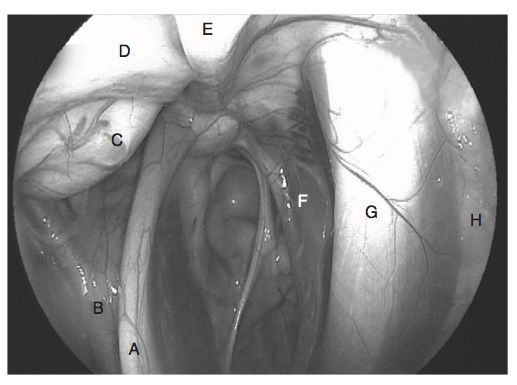

Describe the procedure for a prosthetic laryngoplasty

General anaesthesia Lateral recumbency, head and neck extended Videoendoscope secured transnasally Aseptic prep and drape 10-12cm skin incision ventral and parallel to linguofacial vein, extending caudally from point 4cm cranial to rams of mandible Blunt and sharp dissection with Metzenblum scissors separates linguofacial from lateral margin of omohyoideus along length of incision Elevation of lingufacial vein with Allis tissue forceps allows cleavage plane between sternocephalicus and cricothyroideus - digitally open and enlarge Exposes dorsal aspect of larynx 6-8cm wide malleable retractor placed under linguofacial vein and sternocephalicus muscle used to expose larynx Muscular process of arytenoid under cranial portion of cricopharyngeus and this is exposed by sharply separating the cricopharynxgeus and thyropharyngeus muscles along junction of aponeuroses (alternatively, plane of dissection created off black edge of cricopharynxgeus under vascular plexus that lies over CAD Avoid oesophagus, thyroid gland, laryngeal and thyroid vessels and ventral branch of first cervical and cranial laryngeal nerves Suture materials: braided polyester, with (No. 5 Micron) or without silicone coating, 6mm surgical stainless steel wire, braided lycra, nylon Needle: large swaged on reverse cutting needle or No. 3 Martin uterine reverse-cutting needle Two suture placed Suture placed through cricoid cartilage - walk needle off caudal edge of cricoid 2-3mm lateral to dorsal midline. Needle advanced cranially while avoiding penetration into lumen of larynx. Needle penetrates cricoid 2-3cm cranial to caudal border and 1cm lateral to dorsal ridge Check laryngeal lumen on scope Second suture placed and held with haemostats Suture placed through muscular process.Used No. 6 Mayo needle or No. 6 Martin uterine needle (3mm bone trochar can be used to make tunnel, or 12-16Ga hypodermic needle can make tunnel) Optional to transect tendon of intention of CAD and open cricoarytenoideus articulation and curette joint space (PMMA can also be used) prior to placement of suture Place needle through muscular process from caudomedial to craniolateral direction or caudal to cranial direction Place tension on sutures to remove slack. Tie sutures and visualise larynx. Leave cut ends of suture 1.5-2cm long. Need to achieve 88% of cross sectional rims glottis area Thyropharyngeus and cricopharynxgeus muscles apposed with simple continuous 2-0 absorbable store Apposition of fascia adjacent to linguofacial vein to omohyoideus muscle with simple interrupted or continuous sutures of 2-0 absorbable suture Skin closed with staples or 2-0 non absorbable monofilament suture Stent bandage Can then perform ventriculcordectomy

General anaesthesia

Lateral recumbency, head and neck extended

Videoendoscope secured transnasally

Aseptic prep and drape

10-12cm skin incision ventral and parallel to linguofacial vein, extending caudally from point 4cm cranial to rams of mandible

Blunt and sharp dissection with Metzenblum scissors separates linguofacial from lateral margin of omohyoideus along length of incision

Elevation of lingufacial vein with Allis tissue forceps allows cleavage plane between sternocephalicus and cricothyroideus - digitally open and enlarge

Exposes dorsal aspect of larynx

6-8cm wide malleable retractor placed under linguofacial vein and sternocephalicus muscle used to expose larynx

Muscular process of arytenoid under cranial portion of cricopharyngeus and this is exposed by sharply separating the cricopharynxgeus and thyropharyngeus muscles along junction of aponeuroses (alternatively, plane of dissection created off black edge of cricopharynxgeus under vascular plexus that lies over CAD

Avoid oesophagus, thyroid gland, laryngeal and thyroid vessels and ventral branch of first cervical and cranial laryngeal nerves

Suture materials: braided polyester, with (No. 5 Micron) or without silicone coating, 6mm surgical stainless steel wire, braided lycra, nylon

Needle: large swaged on reverse cutting needle or No. 3 Martin uterine reverse-cutting needle

Two suture placed

Suture placed through cricoid cartilage - walk needle off caudal edge of cricoid 2-3mm lateral to dorsal midline. Needle advanced cranially while avoiding penetration into lumen of larynx. Needle penetrates cricoid 2-3cm cranial to caudal border and 1cm lateral to dorsal ridge

Check laryngeal lumen on scope

Second suture placed and held with haemostats

Suture placed through muscular process.Used No. 6 Mayo needle or No. 6 Martin uterine needle (3mm bone trochar can be used to make tunnel, or 12-16Ga hypodermic needle can make tunnel)

Optional to transect tendon of intention of CAD and open cricoarytenoideus articulation and curette joint space (PMMA can also be used) prior to placement of suture

Place needle through muscular process from caudomedial to craniolateral direction or caudal to cranial direction

Place tension on sutures to remove slack. Tie sutures and visualise larynx. Leave cut ends of suture 1.5-2cm long. Need to achieve 88% of cross sectional rims glottis area

Thyropharyngeus and cricopharynxgeus muscles apposed with simple continuous 2-0 absorbable store

Apposition of fascia adjacent to linguofacial vein to omohyoideus muscle with simple interrupted or continuous sutures of 2-0 absorbable suture

Skin closed with staples or 2-0 non absorbable monofilament suture

Stent bandage

Can the perform ventriculcordectomy